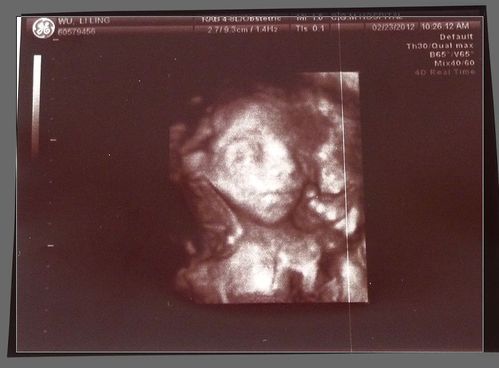

產檢時最令人不清不楚的就是有關於超音波螢幕上所出現的英文縮寫術語